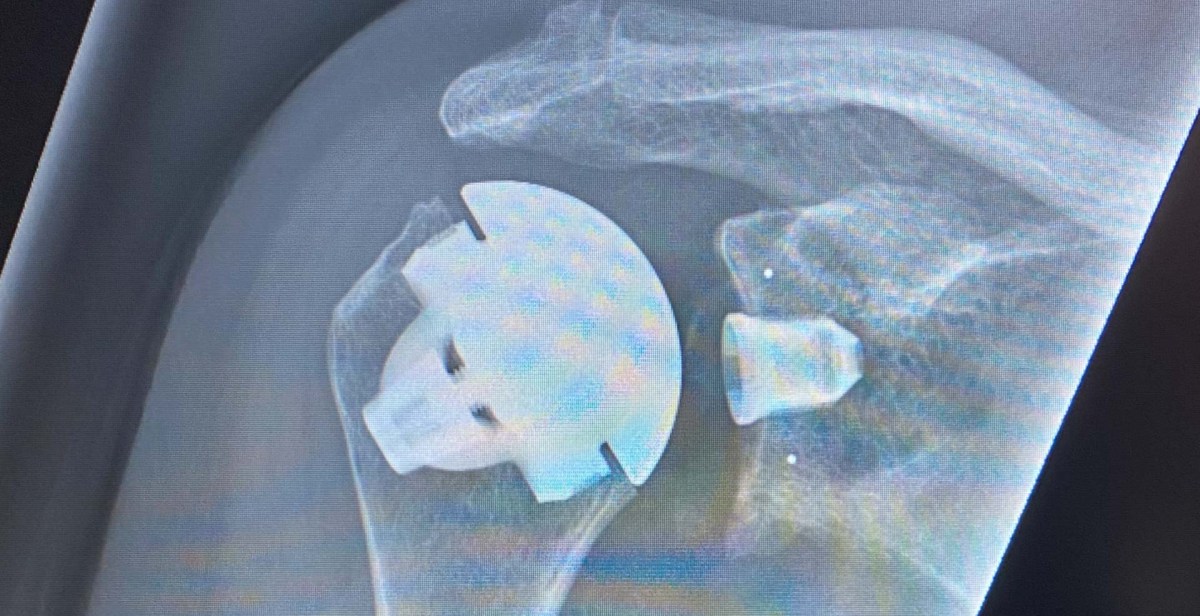

Så blev det eftersom vi fick ändra våra planer, då jag fick tid i slutet av månaden för min efterlängtade axeloperation i Halmstad.

Av kända skäl blev februari en månad på hemmaplan då allt handlade om att sköta om den nya axelleden och vara försiktig med de flesta rörelser. Några utflykter blev det ändå i våra närmsta omgivningar.